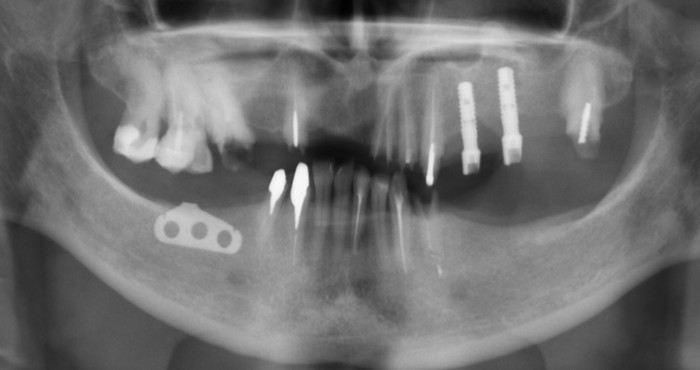

Ниже панорамный снимок зубов пациентки

Вот на кой хер при такой ширине альвеолярной части установили средневековый пластиночный имплантат, остается для меня загадкой.

Итак, после того как были учтены результаты диагностики, консультация ортопеда и (что немаловажно) пожелания пациента (!), было принято решение об удалении всех зубов на верхней и нижней челюсти, в том числе установленных ранее имплантатов. Кроме пластиночного. Его я оставил на десерт.

На верхней челюсти были установлены шесть имплантатов и проведена операция по наращиванию костной ткани – синус-лифтинг (с обеих сторон). Через 2 недели установлены 8 имплантатов на нижней челюсти.

А вот и удаленный пластиночный имплантат.

Спустя четыре месяца были установлены формирователи десны на верхней (снимок слева) и нижней (снимок справа) челюстях.

Панорамный снимок зубов